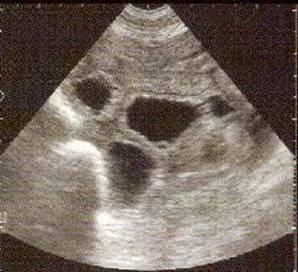

Pregnancy fetal vesicles at 28 days.

It is essential to visualize the fetus within the vesicle.